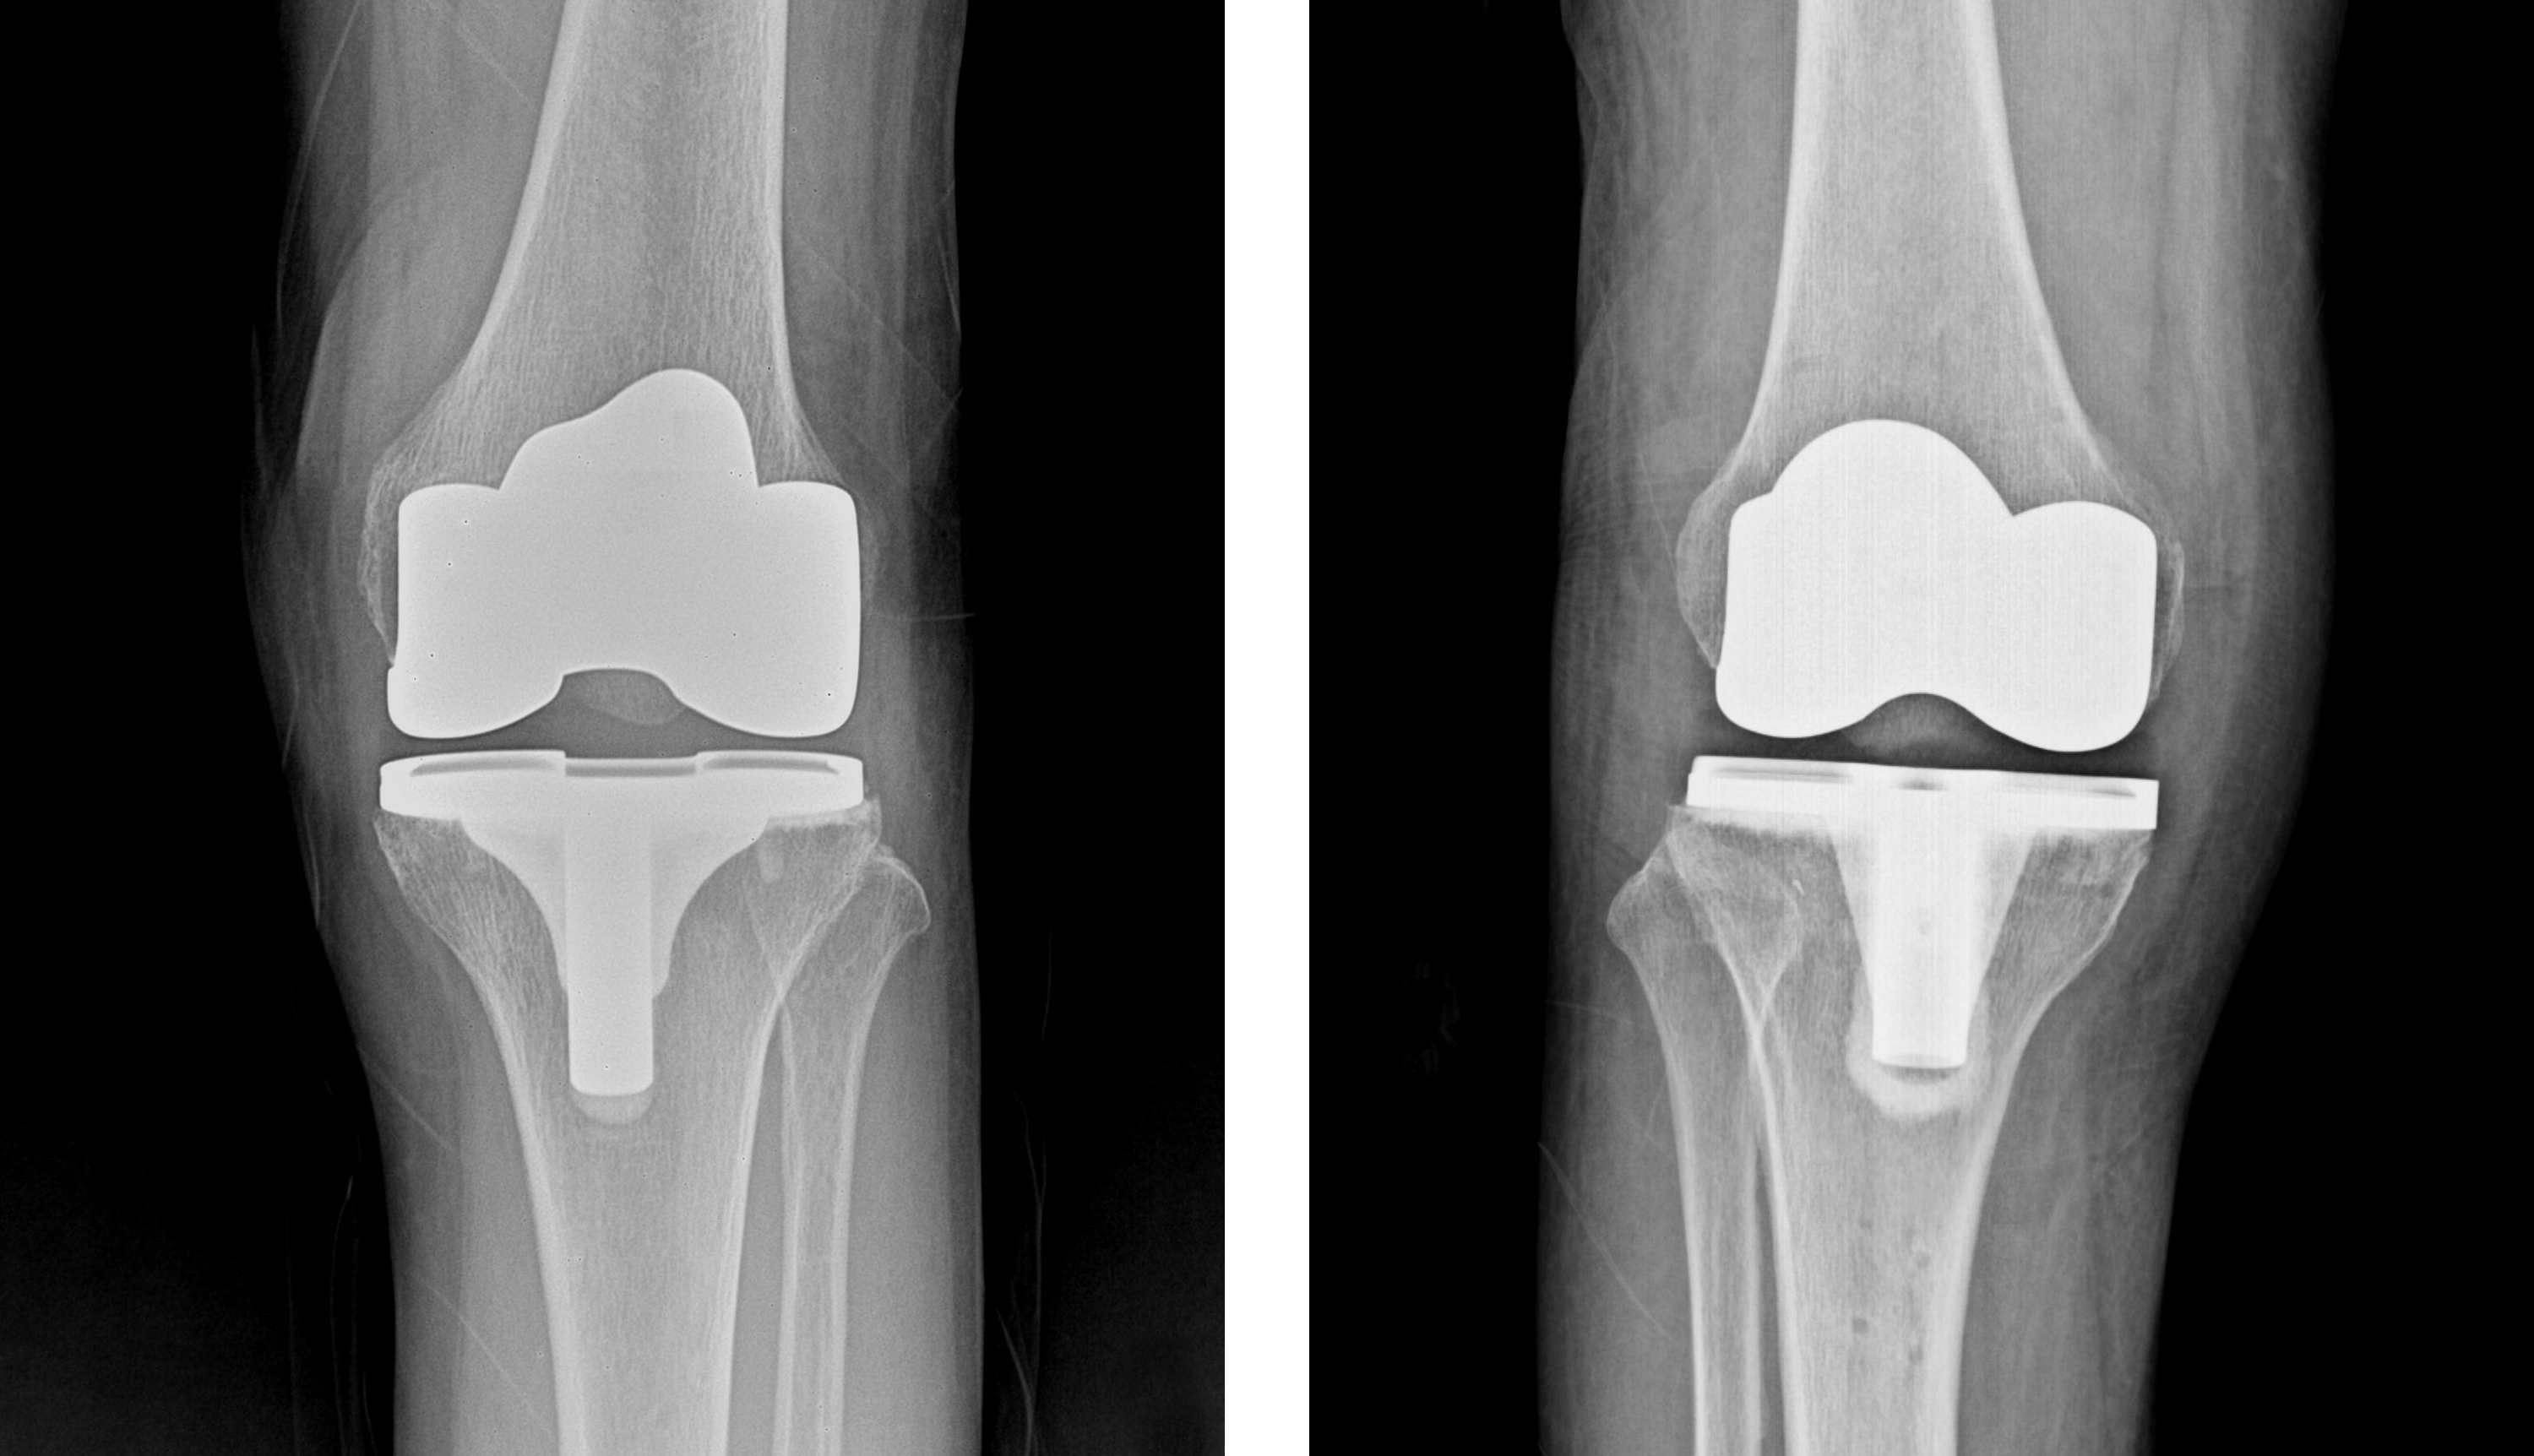

인공관절수술